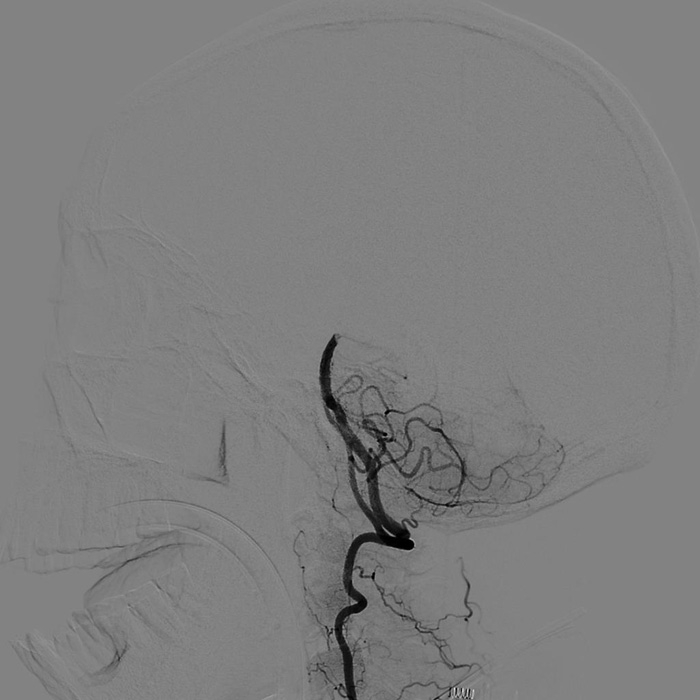

??? 22:10? 王大伯病情進(jìn)一步加重,神經(jīng)外科戴偉民主任醫(yī)師團(tuán)隊、麻醉師和介入室的醫(yī)護(hù)人員全部已經(jīng)到位。全腦血管造影顯示栓塞部位在基底動脈末端,雙側(cè)小腦上動脈及雙側(cè)大腦后動脈開口處完全閉塞。

手術(shù)前血管造影提示雙側(cè)小腦上動脈及雙側(cè)大腦后動脈開口處完全閉塞